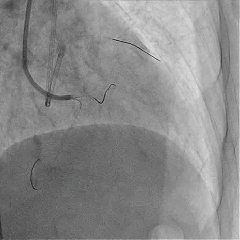

Sion导丝至LCX远端,预扩球囊扩张后,植入支架XIENCEAlpine 2.25*23mm支架一枚

术后造影支架膨胀良好,血流TIMI3级